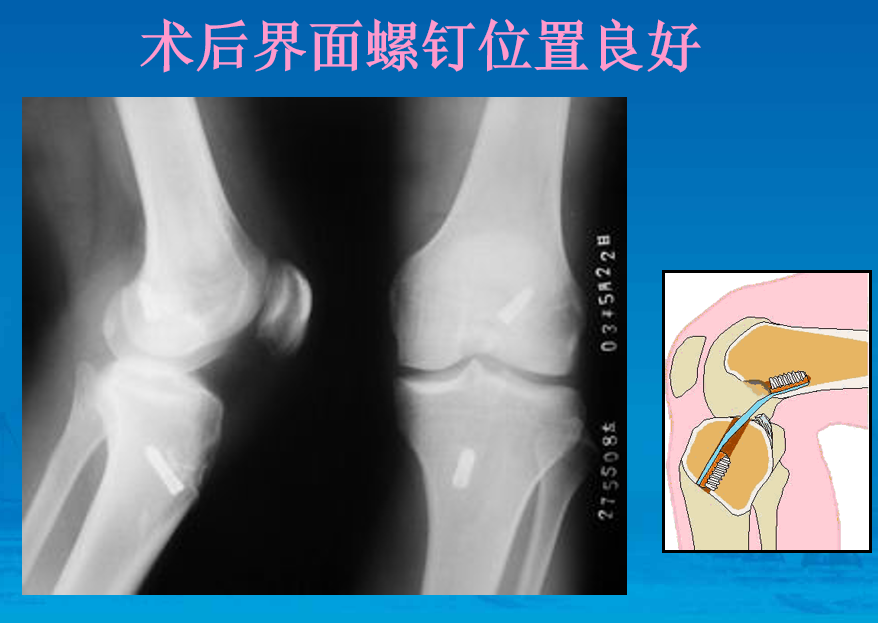

界面螺钉固定移植物

上胫骨端界面螺钉

拉紧B-P-B,并行后抽屉试验,紧张重建韧带,上胫骨端的界面螺钉,必要时可用门型钉或普通螺丝钉加强固定。

用探钩检查,重建韧带张力良好,前抽屉试验阴性,膝关节屈伸正常。

重建术后双束图

重建术后X片